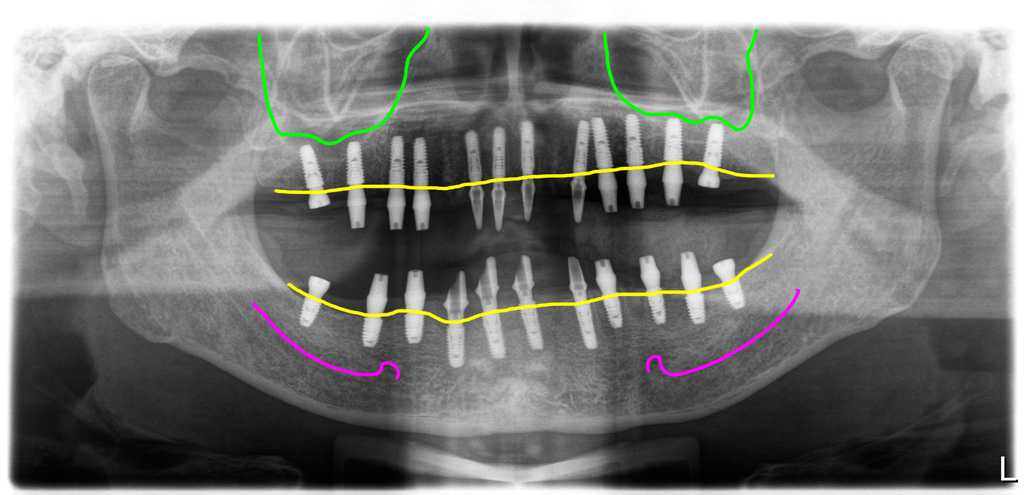

수술날 발치후 즉시식립 당일임시치아

흔들리는 모든 치아를 발치하고 염증을 제거한 다음 즉시식립을 시도했습니다. 위에는 12개, 아래는 11개의 임플란트를 식립했어요.

식립한 임플란트에 지대주를 연결해서 수술당일 임시치아를 만들었습니다. 임시치아를 디자인할 때 고경을 높여서 붕괴된 교합을 수정해 주었습니다.

3개월후 스캔바디 스캔해서 최종보철 디자인

이 분은 교합상태는 좋지 않았지만 뼈상태는 양호하신 편이라 임플란트의 초기고정이 좋아 3개월 후에 2차를 진행했습니다.

최종보철 세팅후 파노라마 마진핏이 좋습니다.

지대주와 지르코니아 디자인을 동시에 진행하고 동시에 세팅하는 방식이라 지대주와 지르코니아크라운의 마진핏이 아주 좋습니다.